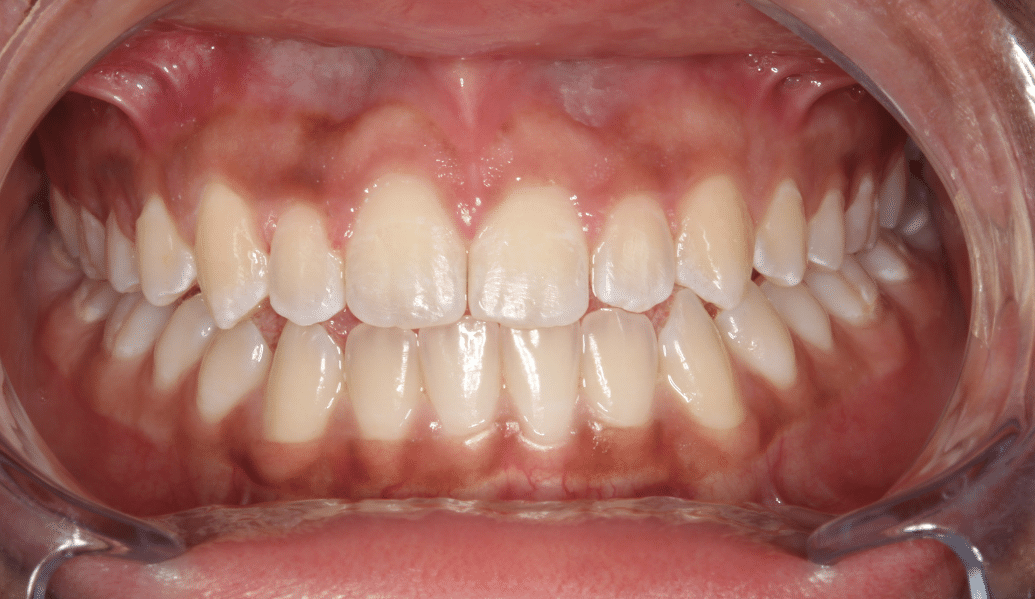

We are proud to help our valued patients to transform their smiles through a wide choice of general and cosmetic dental treatments.

learn moreDelivering life-changing smiles and ensuring excellent dental health.